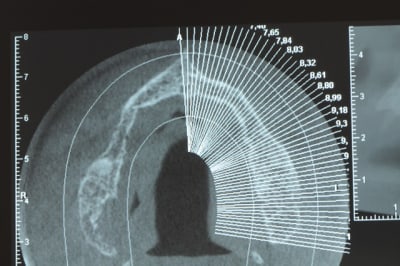

Une petite étude de ton cas D57

Sous réserves bien sur de voir l’animal en vrai

Les zones exploitables radiologiquement parlant:

Coupes implant

2,3 40100

4,96 35130 avec sinus lift mais difficile

5,25 35150

6,02 35130

6,78 35115 après réduction de hauteur de crête

7,26 35115 après réduction de hauteur de crête

8,51 35150

10,43 40115 ou 50115

11,10 40115

Ce qui nous fait 9 implants possible évidement avec un comblement de sinus on augmenterait encore les zones implantable mais ce n’est pas le but recherché, avec 8 (4+4) il doit être possible de faire une belle barre support de complet